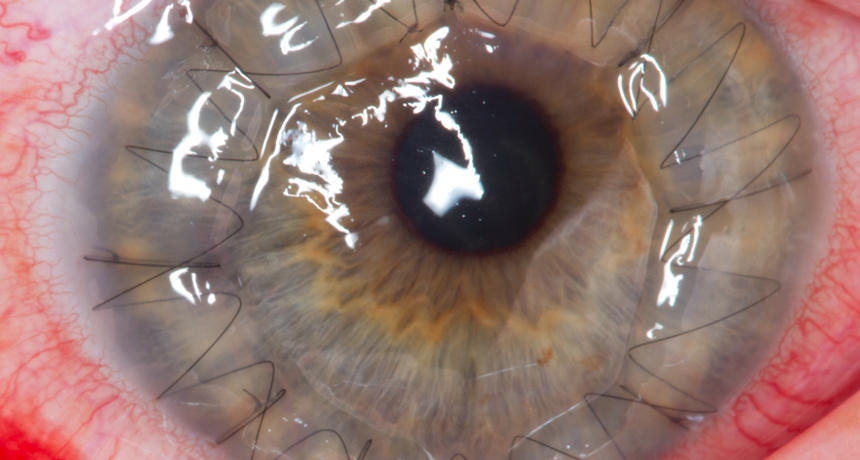

EYE OPENER Women who receieve corneal transplants are more likely to reject them if their donors are male.

Megor1/Wikimedia Commons (CC BY-SA 3.0)